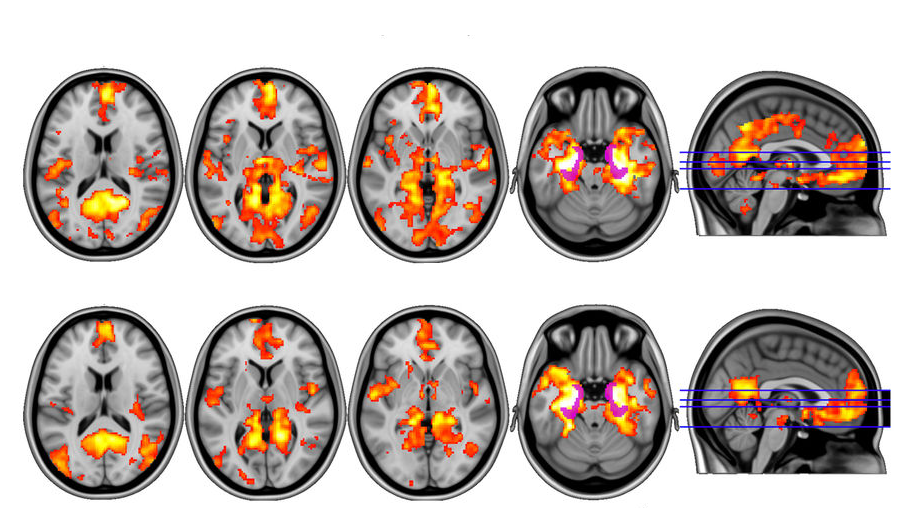

Magic Mushrooms Hit Brain's 'Reset' Button in Depressed Patients Inverse Mushrooms For Brain Injury (1) tryptamines like psilocybin (which is converted to psilocin after. Psilocybin is a classic psychedelic compound that may have. in vitro and in vivo studies suggest psychedelics may influence the future of brain injury treatment in both the. liberty caps produce the psychoactive compounds psilocybin, psilocin, and baeocystin, and are one of. the classical psychedelics include: . Mushrooms For Brain Injury.